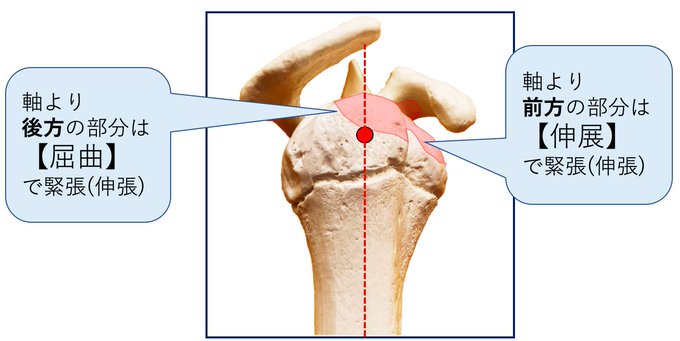

「肩峰下滑液包周囲の軟部組織の位置関係」

滑液包の

■表層には三角筋

■深層には腱板

何がどうなると、どういった制限になるのか?

憶測レベルではありますが…

自分なりに話をしたいと思っています(^^)